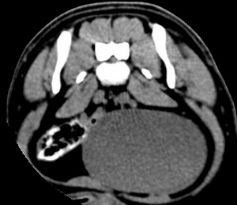

L7-S1 双侧椎间孔狭窄

CT横断扫描图上可见分别在L4-L5、L5-L6、L7-S1处椎间盘突出,压迫硬囊膜和椎间孔,导致相应的椎间孔狭窄,椎间孔内的神经受到压迫,导致该犬后肢无力及尿潴留。